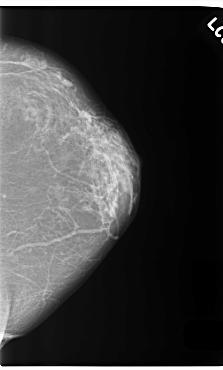

C_0255_1.RIGHT_CC

RIGHT_CC LINES 5832 PIXELS_PER_LINE 3824 BITS_PER_PIXEL 12 RESOLUTION 50 OVERLAY